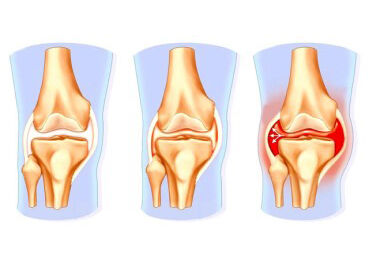

Причины и лечение травм коленного сустава